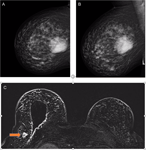

Synchronous malignant phyllodes tumour and invasive lobular carcinoma—case report and review

Henry To and others

Journal of Surgical Case Reports, Volume 2018, Issue 10, October 2018, rjy258, https://doi.org/10.1093/jscr/rjy258